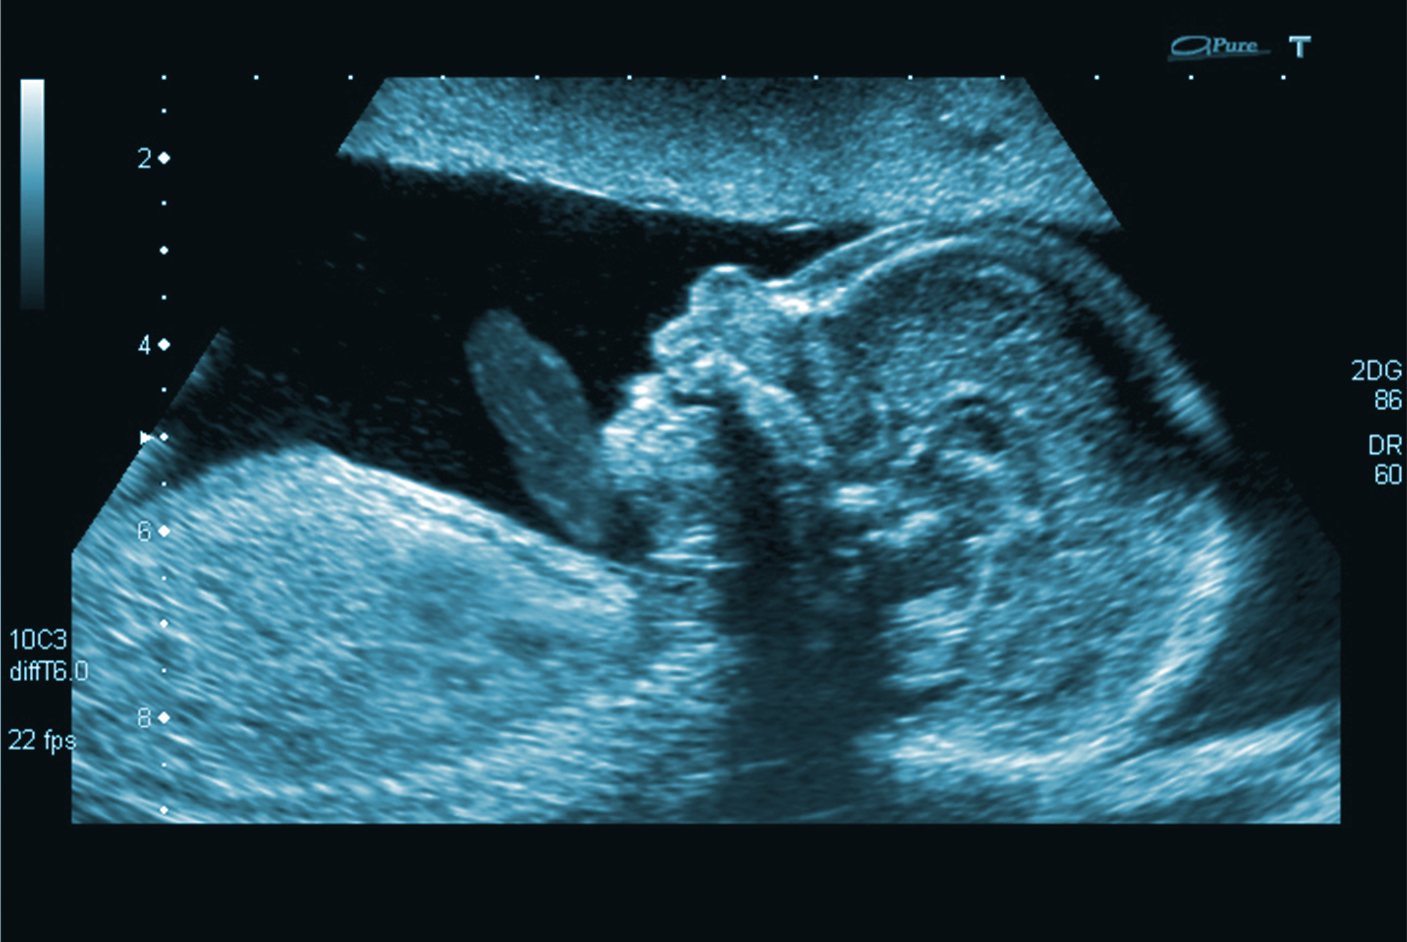

Bildgebung und Therapie mit Ultraschall haben in der Medizintechnik große Bedeutung. In dieser Vorlesung werden die Grundlagen der Ultraschallphysik und darauf aufbauend technische Elemente und Konzepte von Systemen für die medizinische Diagnostik und Therapie behandelt. Viele der vermittelten Inhalte zur Ultraschalltechnik sind dabei auch auf industrielle Anwendungen, wie z.B. die zerstörungsfreie Werkstoffprüfung anwendbar.